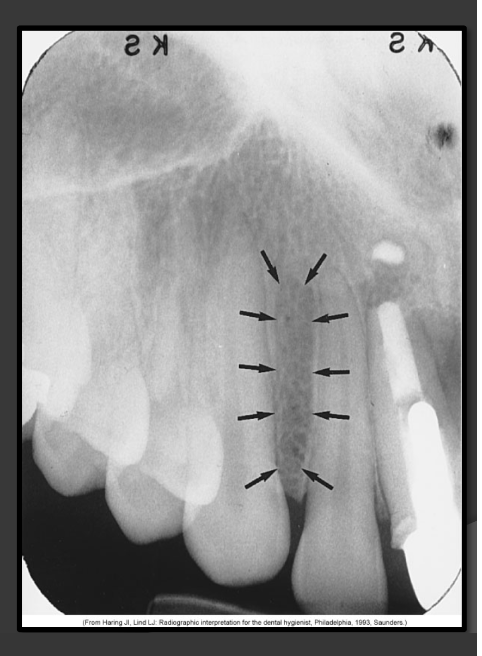

How does the mandibular canal present in a radiograph?

It is a radiolucencent band that follows the contour of the mandible that runs under the teeth.